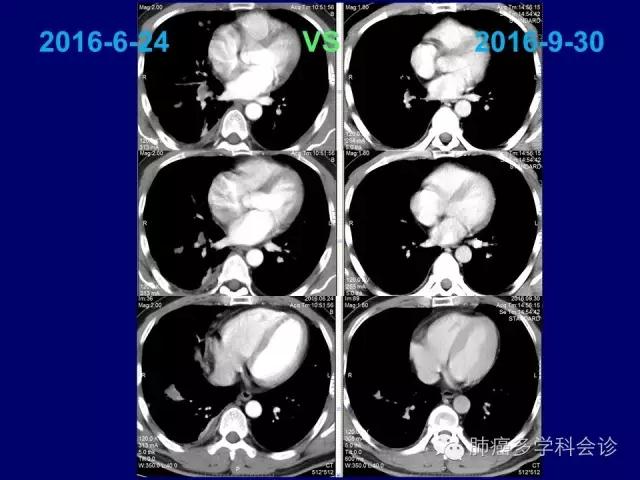

对PEM为基础的化疗敏感

化疗耐药后再使用ALK抑制剂,会明显推迟后者耐药的形成,充分发挥化疗和靶向治疗各自潜能和“相加”(?)作用。41.jpg